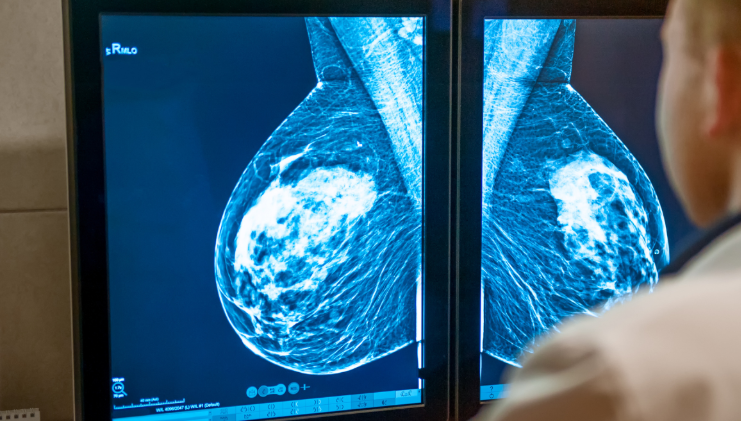

유방을 단면으로 보면, 유선이 복잡하게 얽혀 있고 그 사이를 지방 조직이 감싸고 있습니다. 지방은 영상 검사에서 어둡게, 유선은 밝게 보이는데, 치밀유방의 경우 밝은 부분이 넓게 퍼져 있습니다. 이런 이유로 의학 영상에서는 유방이 전체적으로 ‘하얗게’ 보이는 특징이 있습니다.

유방촬영(맘모그래피)에서는 유선 조직이 많을수록 하얗게 보입니다. 문제는 혹이나 종양도 같은 흰색으로 나타난다는 점입니다. 이 때문에 치밀유방에서는 이상 병변이 가려질 가능성이 있어 영상의학과에서는 이를 별도로 표시합니다. 하지만 이 결과만으로 질병을 판단하지는 않으며, 정확한 평가는 초음파나 다른 검진 결과와 함께 종합적으로 이뤄집니다.